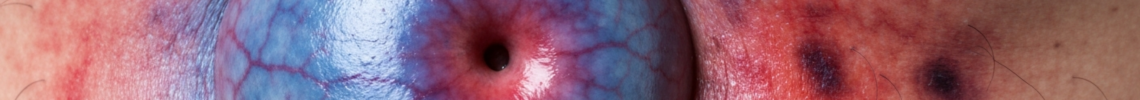

• Vascularity: Increased visibility of blood vessels might be noted under the stretched skin, particularly in individuals with fair complexions.

• Discoloration (Rarely, indicating complication): While typically the skin color remains normal, a reddish or purplish hue can be a critical visual symptom indicating a serious complication such as incarceration or strangulation, requiring immediate medical attention. Umbilical hernia symptoms pictures showing such discoloration are crucial for emergency recognition.

• Erythema (Redness): Localized redness over the hernia sac is a concerning sign, suggesting inflammation, infection, or, more critically, strangulation due to compromised blood supply. Umbilical hernia pictures showing erythema warrant immediate medical attention.

• Cyanosis (Bluish Discoloration): A bluish or purplish discoloration indicates severe compromise of blood flow to the incarcerated tissue within the hernia sac, a sign of strangulation and a medical emergency. These are vital signs in umbilical hernia symptoms pictures for emergency recognition.

• Erythema (Sudden, Intense Redness): Rapid onset of intense redness over the hernia, often accompanied by warmth and tenderness, is a strong sign of inflammation or strangulation.

• Bluish or Purplish Discoloration (Cyanosis): This is an emergency sign indicating that the blood supply to the incarcerated tissue (often bowel) within the hernia sac is severely compromised or completely cut off. This requires immediate surgical intervention. “Skin rash umbilical hernia images” showing cyanosis are a critical alert.

• Bruising: Darkening of the skin resembling a bruise can also indicate tissue damage or bleeding within the hernia sac due to strangulation.